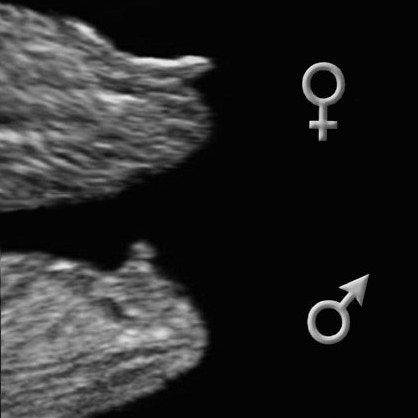

алина

Девочки всем привет как думаете мальчик или девочка, узист сказала есть бугорок что то похожее на мальчика, но это не точно. А так хочется сыночка)))

25.08.2020